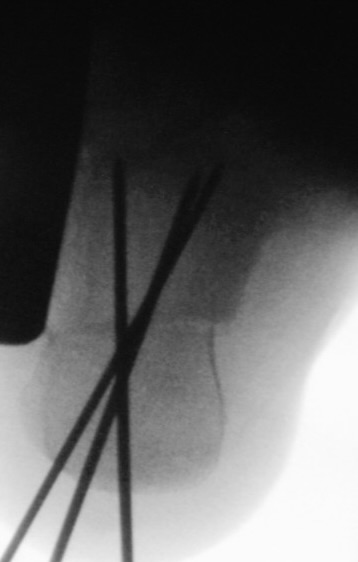

Zusätzlich schränken Wachstumsfugen die Wahl der Osteosynthese ein. Eine die Fuge kreuzende Osteosynthese ist ausschließlich mit Kirschner-Drähten möglich (Abb. 3).

Abb. 3 a-j: Beispiel einer Calcaneusverschiebeosteotomie mit offenen Wachstumsfugen und der entsprechenden Osteosynthese mit Kirschner Drähten. Lokalisation der Osteotomie (a), Lage der Fräse (b-d), Drahtlage mehrere Ansichten (e-h), Heilung der Osteotomie 4 Wochen postoperativ und Entfernung der Drähte (i-j).

Zum Lesen der Bildbeschreibung und zur Vollansicht bitte die Bilder anklicken. Bilder: A. Helmers.